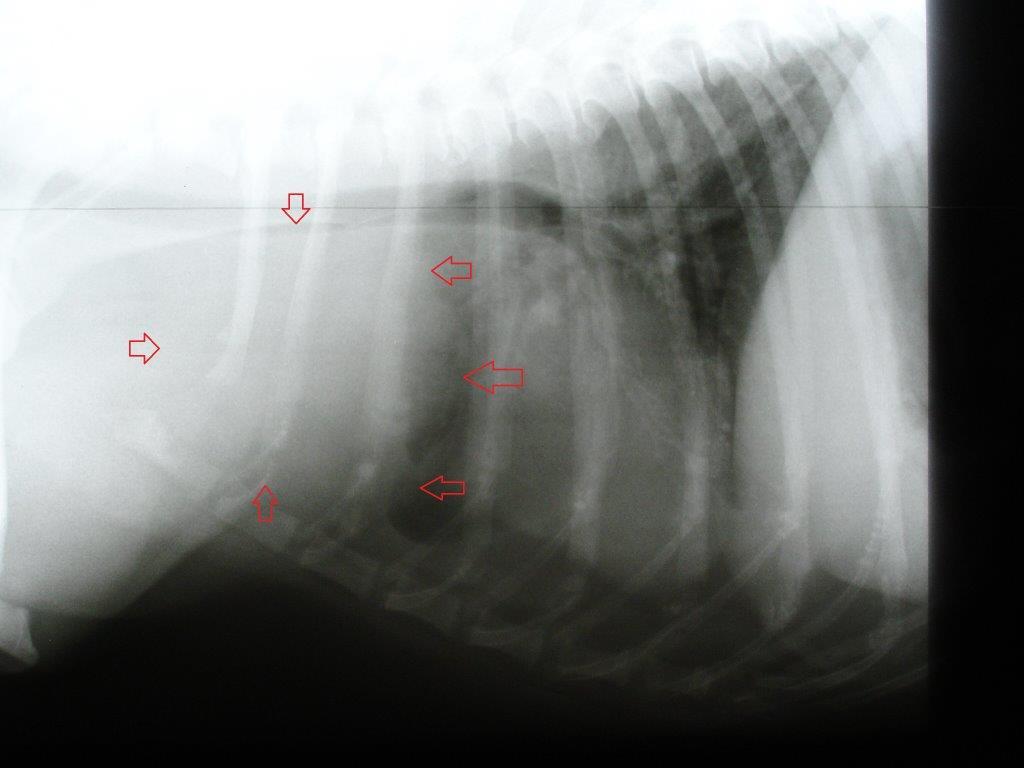

Die Analdrüsen und die äußerlich tastbaren Lymphknoten waren unauffällig. Daraufhin wurden Röntgenaufnahmen von Brust- und Bauchraum angefertigt. Im Brustkorb befand sich vor dem Herzen eine tennisballgroße Zubildung. Zur Diagnosestellung wurde dieser Tumor unter Ultraschallkontrolle mit einer Spritze punktiert und Zellmaterial gewonnen. Dieses Feinnadelaspirat wurde zu einem spezialisierten Tierpathologen geschickt. Der Befund: „Malignes Lymphom“. Das maligne Lymphom kann in einen B- und T-Zell-Typ eingeteilt werden, je nachdem welche Lymphozytenfraktion betroffen ist. In diesem Fall war es das schwieriger zu therapierende T-Zell-Lymphom. Die Ultraschalluntersuchung des Bauchraumes zeigte keine Veränderungen im Bereich von Leber, Milz und den anderen Lymphknoten des Bauches.